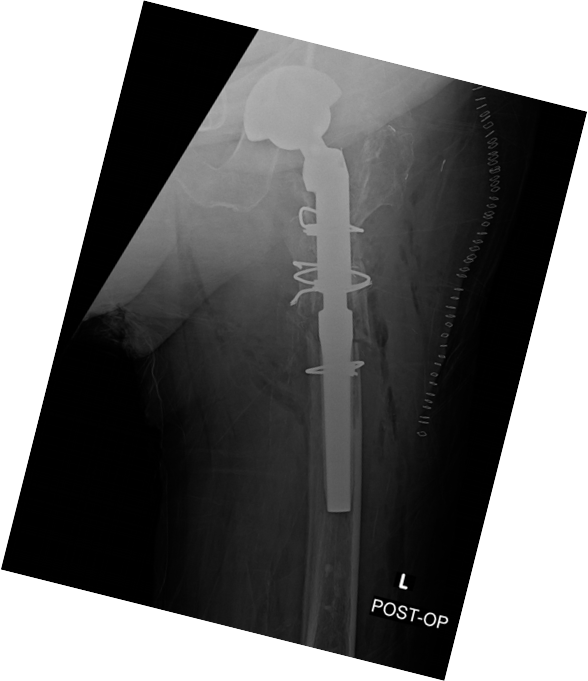

Case presentation: 70 yo F presents to clinic s/p short CMN of left intertroch fx at outside facility in Aug 2022 with worsening left hip pain, inability to bear weight. No pertinent PMHx. Workup and treatment plan?

Infxn workup negative, Lateral approach used, Wagner osteotomy to facilitate nail removal, autograft from femoral/neck 50 cc allograft to graft defect in posterior column, multihole cup/screws w/ dual mobility, modular fluted tapered stem.

ETO was performed 15cm in length, Cables were deeply imbedded in bone and had to be cut through with ETO, trephine over the remaining distal stem. Revised to modular fluted tapered stem.